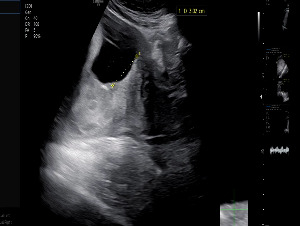

그리고 마지막, 가장 중요한 순서가 기다리고 있었다. 태반 위치를 정확히 확인하는 질내 초음파 검사.

잠시 후, 선생님의 목소리가 차분하게 울렸다.

“태반이 4cm 정도 떨어져 있습니다. 이 정도면 자연분만도 가능합니다.”

떨리지만 기쁨이 묻어난 목소리였다. 나도 연신 “정말요?”를 되뇌며 초음파 화면을 뚫어지게 바라봤다.

화면 속 찹쌀이는 고개를 살짝 돌린 채, 통통한 볼을 내밀고 있었다.

KakaoTalk_20250928_205002017.jpg 걱정말라며 태반뒤에서 얼굴을 보여주는 찹쌀이